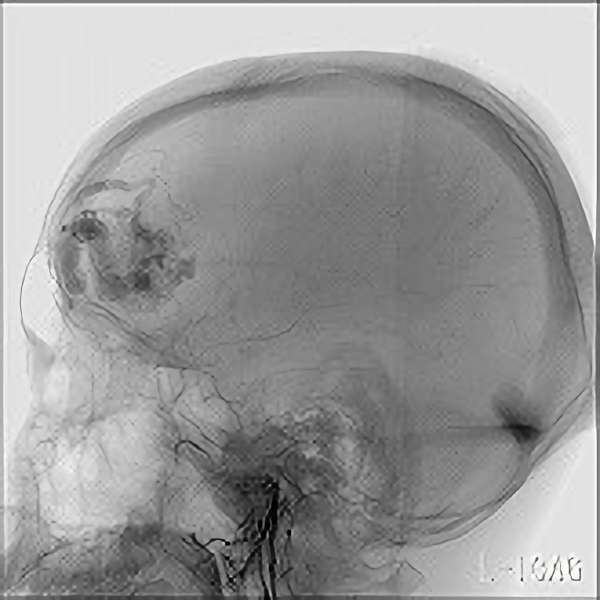

'19年5月

30代

富永/久貝

右中小脳脚 出血再発

SM 3(S1,E1,V1)

米国の病院

No.359 モニタリング

No.359 手術前

No.359 手術中

No.359 手術後

出血既往があり。2回の手術前血管内手術の後に、

Lateral transpeduncular approachにより再々出血予防を目的に

摘出手術を行う。完全摘出であることを確認した。

手術による合併症や後遺症なしで退院した。経過良好。